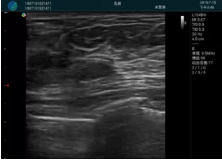

腺體內(nèi)部清晰顯示一低回聲塊影,形態(tài)不規(guī)則,邊界模糊,邊緣呈毛刺狀,內(nèi)部見(jiàn)砂礫樣鈣化

M20引導(dǎo)下穿刺活檢術(shù)

M20引導(dǎo)下平面內(nèi)穿刺取出的腫塊組織

M20查看:囊內(nèi)回聲均勻,邊界清晰,囊壁光滑

M20引導(dǎo)抽吸術(shù)后囊腫消失,原區(qū)域空腔形成,脂肪層與腺體層架構(gòu)發(fā)生改變